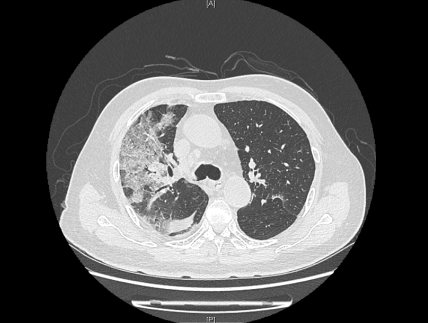

来院时,患者感染新冠病毒5天,持续发烧不退,出现了憋气、意识不清。入院后持续监察发现,患者肺部CT逐步呈“白肺”状态,血气氧分压一度降至50mmHg,“正常血气氧分压为80-100mmHg,低于60mmHg,在临床上就可诊断为I型呼吸衰竭。”感染性疾病科主任林明贵说。同时,患者合并长年慢阻肺、高血压病史,以及少见的血液病单克隆丙种球蛋白病、心梗病史、甲状腺功能减退、肾动脉狭窄等疾病。

患者肺部CT检查图像

在多学科联合保驾之下,老人入院后5天病情出现了转机,成功解除无创呼吸机,并逐步从高流量吸氧降至经鼻导管吸氧。“当时看到肺部影像时,心已经凉了半截,做好了最坏的思想打算。”患者的儿子说,老人生病前爱好打乒乓球,希望此次康复后,重新回归他热爱的球场。